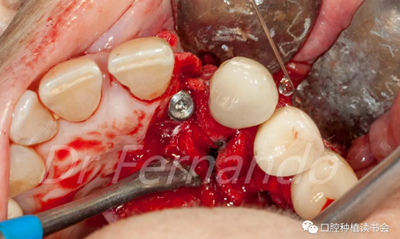

在骨粉上方覆蓋 Osgide? 可吸收膠原膜(Curasan?-科盧森) ,用絲線嚴(yán)密關(guān)閉傷口(圖 22 )

圖22 植骨區(qū)覆蓋可吸收膠原膜,關(guān)閉創(chuàng)口